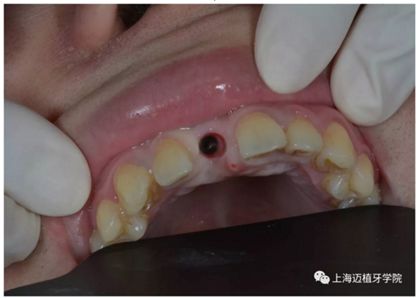

3月后恢復(fù)良好,上愈合基臺(tái)

2周后袖口成形

戴牙前口內(nèi)照片:

去除愈合基臺(tái):